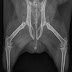

Kurpitsansiemen kurkussa, heinä silmässä ja kivi virtsaputkessa - tervetuloa jälleen marsujen ihmeelliseen sairausuniversumiin!